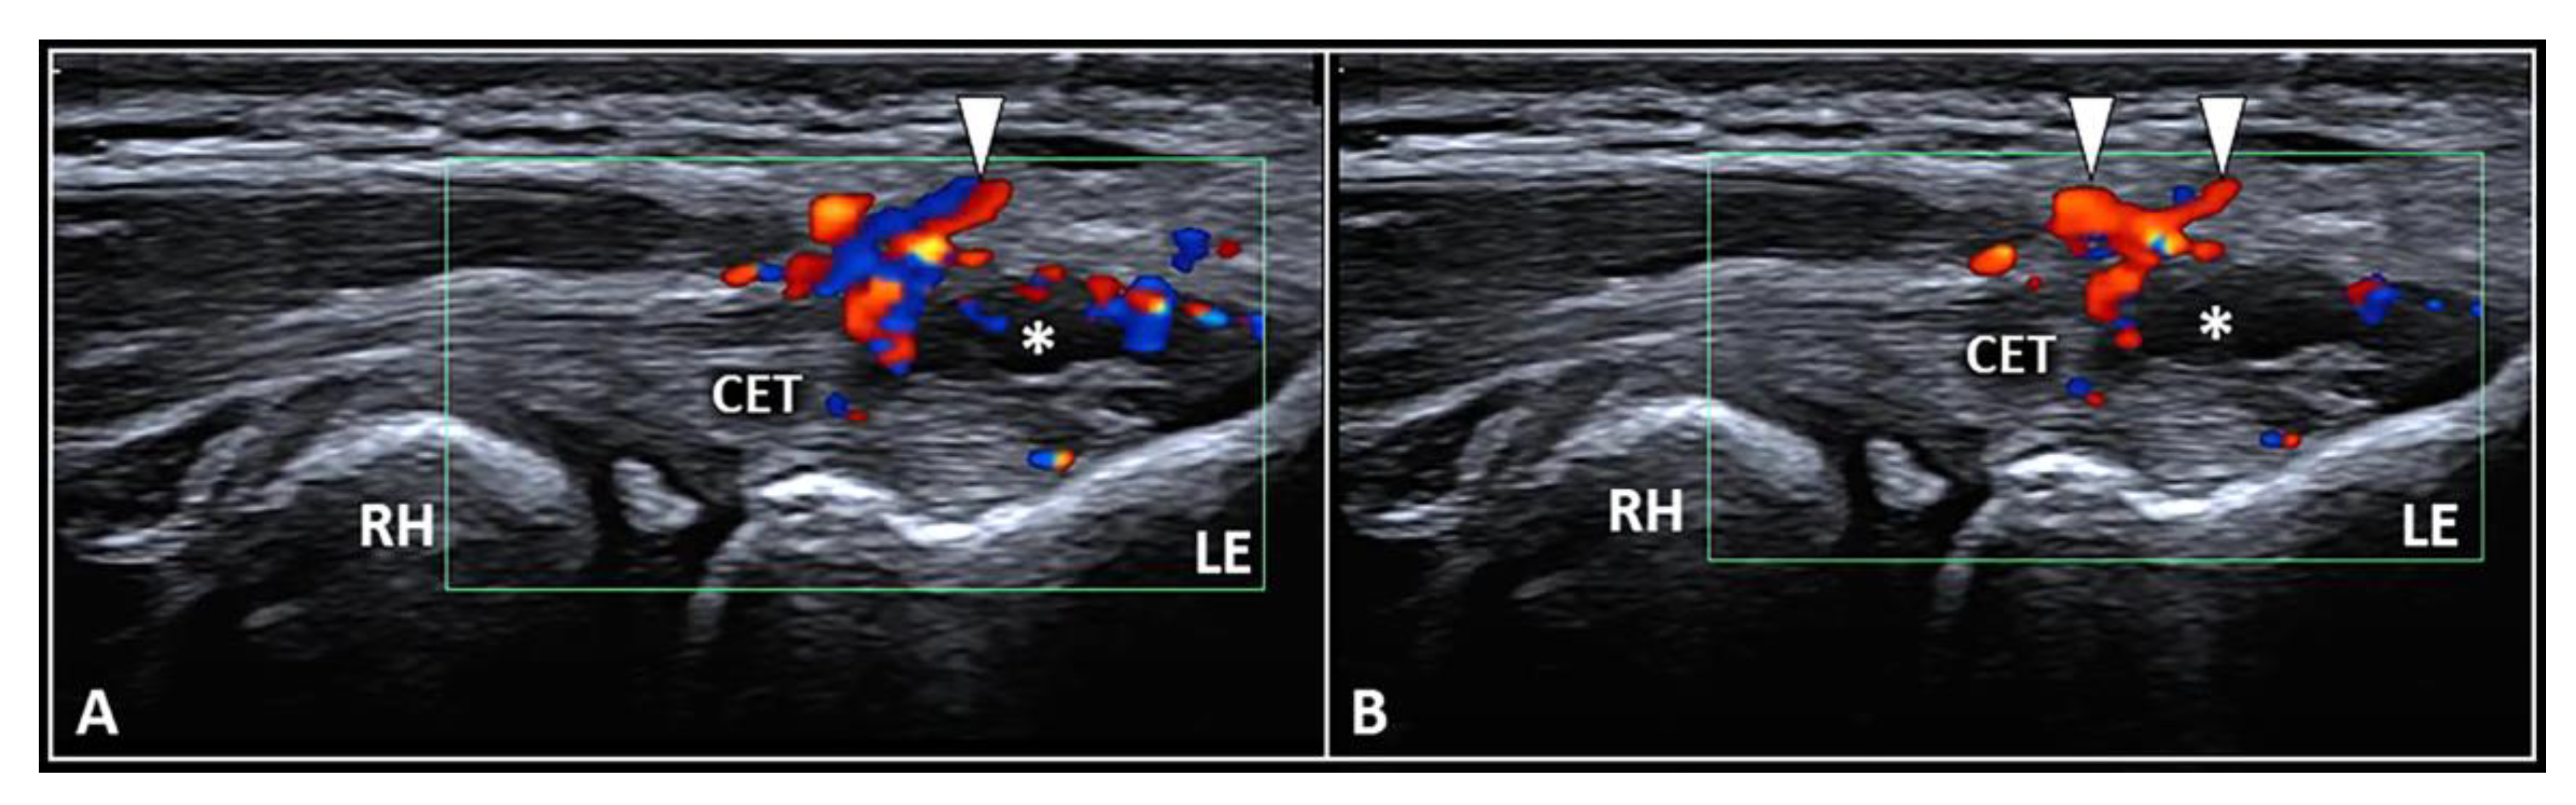

3.1. Peritendinous Injection

| Peritendinous | Interface between the CET and the forearm fascia | High-volume hydrodissection detaching the fascia from the underlying CET * |